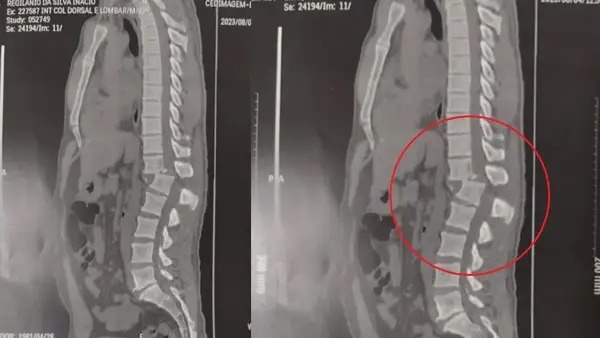

Regilânio submeteu-se a uma operação no último sábado (5), visando estabilizar sua coluna vertebral e aliviar a compressão da medula. O propósito da cirurgia é permitir que ele pudesse manter-se sentado e reduzir as sensações de dor.

Atualmente, ele é capaz de se alimentar de maneira independente e está passando por sessões de fisioterapia. Além disso, ele já é capaz de se sentar após a cirurgia.